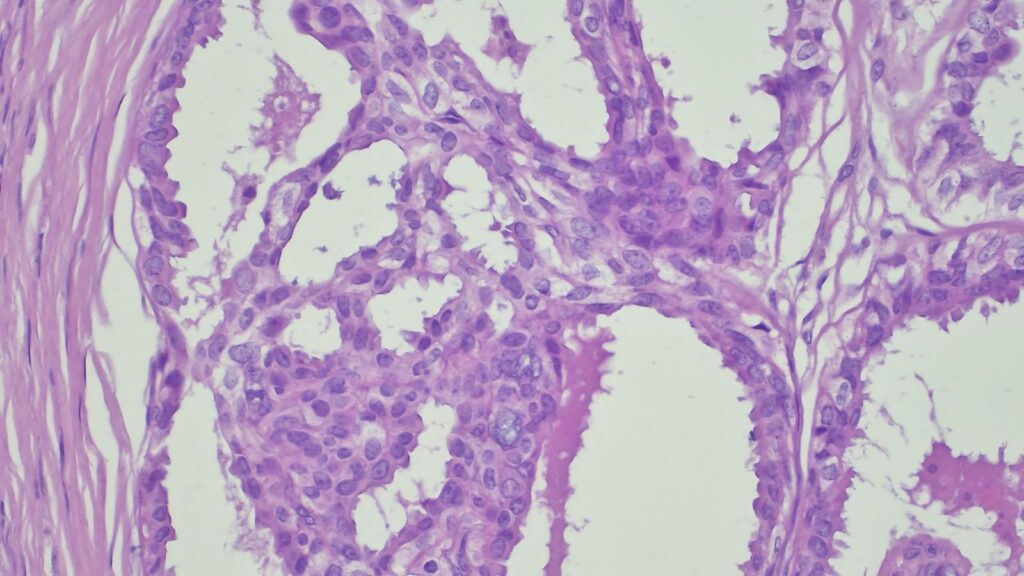

【病理形态学大解密:寻找良性证据】 仔细阅片后,专家指出了以下几个至关重要的形态学特征(见附带病理切片图):

✅ 腺体发育良好,呈圆形和分叶状结构。 ✅ 边缘虽略不规则,但整体呈推挤性(pushing)和局限性生长。 ✅ 无弥漫性浸润结构。 ✅ 无促结缔组织增生性间质反应(No desmoplastic stromal reaction,这是排除浸润癌的核心点)。 ✅ 细胞学形态温和(Bland cytology)。 ✅ 在慢性炎症和纤维化的背景下,仅见单个典型的核分裂象。 在病变外周,腺体表现出被瘢痕样间质压迫和塑形的特征,而不是破坏性或浸润性生长。